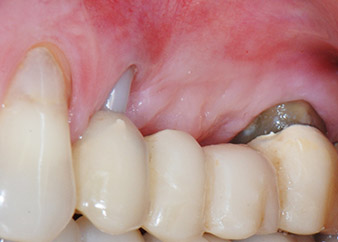

Una paziente donna di 58 anni lamentava dolore e aumentata mobilità del dente di appoggio del ponte 24. Era presente infiammazione periodontale con tasche di profondità di 7 mm a livello mesiobuccale e di più di 12 mm a livello distale, nonché coinvolgimento di terzo grado della forcazione. Inoltre, la radiografia rivelava una lesione periodontale estensiva attorno alla regione apicale del dente pretrattato 24 (in altro luogo) a livello endodontico (Fig. 1).

Un mese più tardi, nel giorno programmato per l'intervento, il dolore e l'infiammazione in corrispondenza del dente 24 erano minimi, ma era ancora presente mobilità di classe 2 secondo Miller. Dopo l'apertura dei lembi e la pulizia del tessuto periapicale e periradicolare infetto, l'estensione della mancanza ossea si è resa evidente (Figg. 2 e 3).

Tutto il tessuto osseo vestibolare e distale era mancante in corrispondenza della radice buccale. La possibilità di attacco era essenzialmente ristretta alla radice palatale, evidenziando la prognosi negativa preliminare. Anche il dente 27 mostrava un punto di attacco orizzontale ridotto e una rarefazione apicale minima (cfr. Fig. 1), senza sintomi clinici.

Le figure 17 e 18 mostrano il risultato clinico due mesi dopo l'intervento chirurgico. Il dente 24 mostra mobilità ridotta di classe 1 secondo Miller e i tessuti molli sono privi di infiammazione. A questo punto l'utilizzo della sonda è stato evitato per impedire una nuova infezione e per non disturbare l'attacco epiteliale. Era stata programmata una visita di controllo al rientro e il posizionamento dei perni di guarigione sei mesi dopo l'inserimento degli impianti.